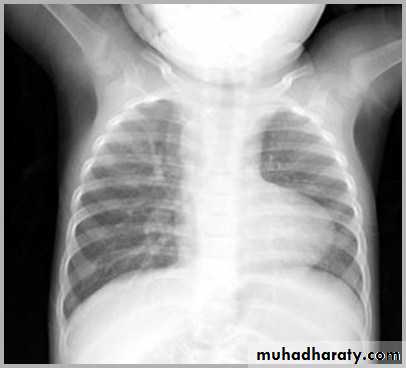

Transposition of the great arteries (TGA) is the most common cyanotic congenital cardiac anomaly with cyanosis in first 24 hours of life. It accounts for up to 7% of all congenital cardiac anomalies

Chest radiograph

A frontal chest radiograph classically shows cardiomegaly with a cardiac contours classically described as appearing like an egg on a string . There is often an apparent narrowing of the superior mediastinum as result of the aortic and pulmonary arterial configuration .

Egg-on-a-string sign ( TGA )